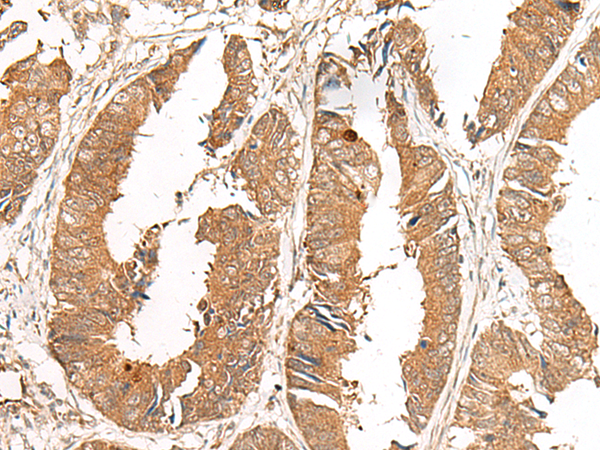

分类: 科研抗体货号: P13465别名: GA; GLS; LGA; hLGA应用: WB,IHC反应种属: Human, Mouse, Rat